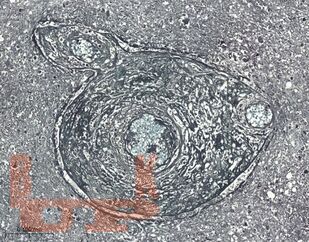

Учебное пособие посвящено актуальным вопросам патогенеза, клинического течения, диагностики и лечения церебрального токсоплазмоза у ВИЧ-инфицированных пациентов. Особое внимание уделено вопросам дифференциальной диагностики церебрального токсоплазмоза от другой патологии нервной системы, в том числе опухолей головного мозга, нарушений мозгового кровообращения, воспалительных заболеваний. В пособии представлены собственные клинические наблюдения многоочаговых и солитарных форм церебрального токсоплазмоза.